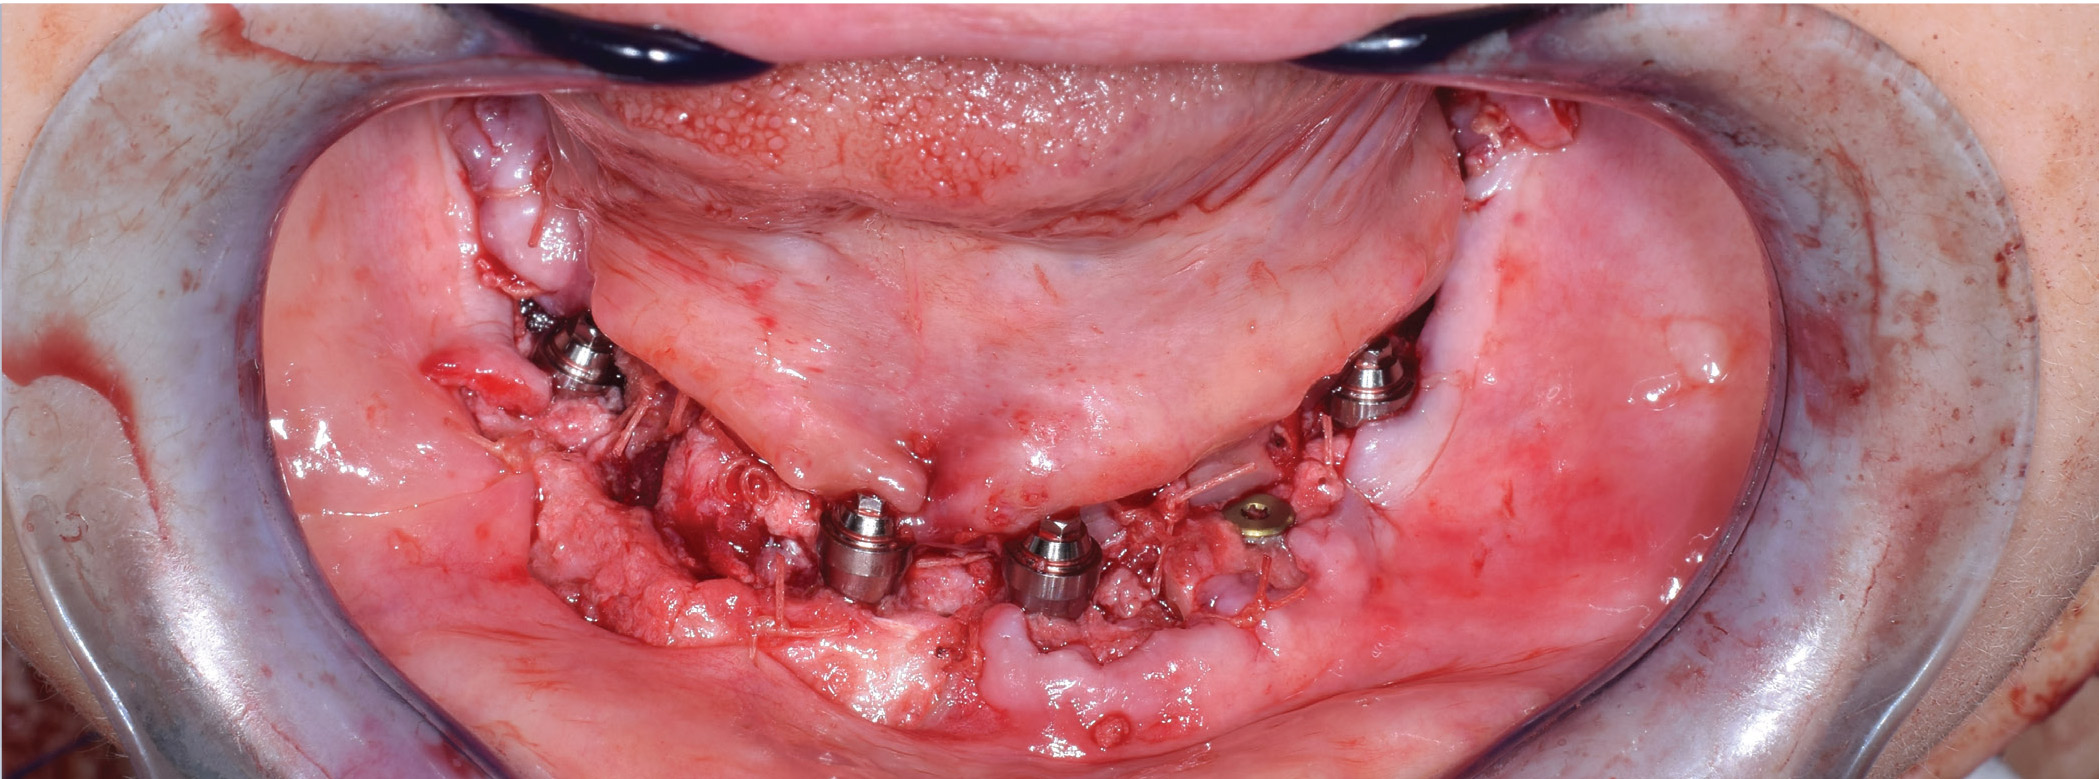

After implants were inserted, multiunit abutments and temporary copings were placed. In this case, six Nobel Biocare NobelActive implants were placed, but only four were used for the provisional prosthesis. The remaining two implants were reserved for the final prosthesis (Fig. 9).

Implants were placed through the inferior border of the fibula for bicortical stabilization. The fibula cutting guide was then used to make closing ostectomies on the fibula to create the curvature of the neomandible (Fig. 10). The three fibula segments were attached to a custom-milled plate while using the hybrid prosthesis as a template to ensure the implants emerged through the planned access opening (Fig. 11).

Building a Mandible Figure 1: Preop Panorex shows tumor of the anterior mandible. Figure 2: Virtual plans showing three fibula segments and six implants angled to emerge through the occlusal surface of the preoperative dention. Figure 3: The final virtual construct with fibula, implants, and custom-milled titanium plate. Figure 4: The fibula cutting guide with slots to cut the fibula into three segments. Six guide holes are for implants and an additional six guide holes are for placement of fixation screws. Figure 5: Printed model of neomandible with implants and custom-milled titanium plate. Figure 6: Specimen removed Figure 7: Fibula exposed through a lateral leg incision. Figure 8: Guide attached to fibula to place implants while still perfusing on the leg. Figure 9: Six implants placed into fibula (although only four will be used for the provisional prosthesis).